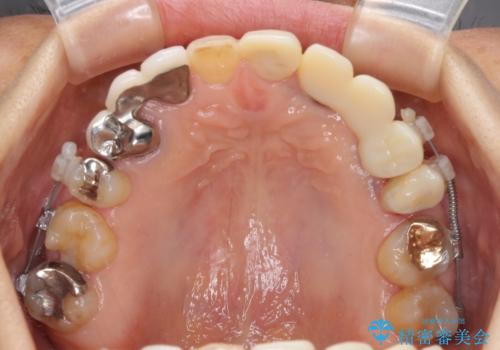

上顎はほぼ全ての歯をセラミッククラウンにて補綴治療を行う必要があるため、気になるデコボコや深い咬み合わせを改善するために下顎と上顎の臼歯部の矯正治療を行うこととしました。

並行して左下にはインプラントを埋入し、矯正治療を終えると同時に補綴治療を行うこととしました。

過蓋咬合(下顎前歯が隠れてしまうほどの深い咬み合わせ)のため、スムーズに歯が動かず矯正治療に時間がかかりましたが、無事に仕上げることができました。